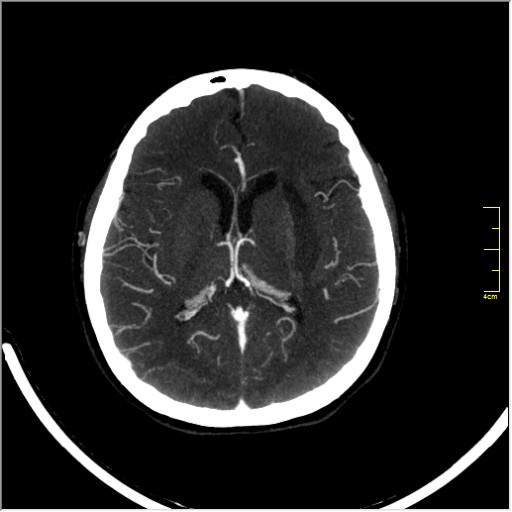

КТ ангиография головного мозга

Стандартная процедура в современной работе КТ кабинета, весьма несложна в исполнении.

Сканы представленны в режиме MIP.